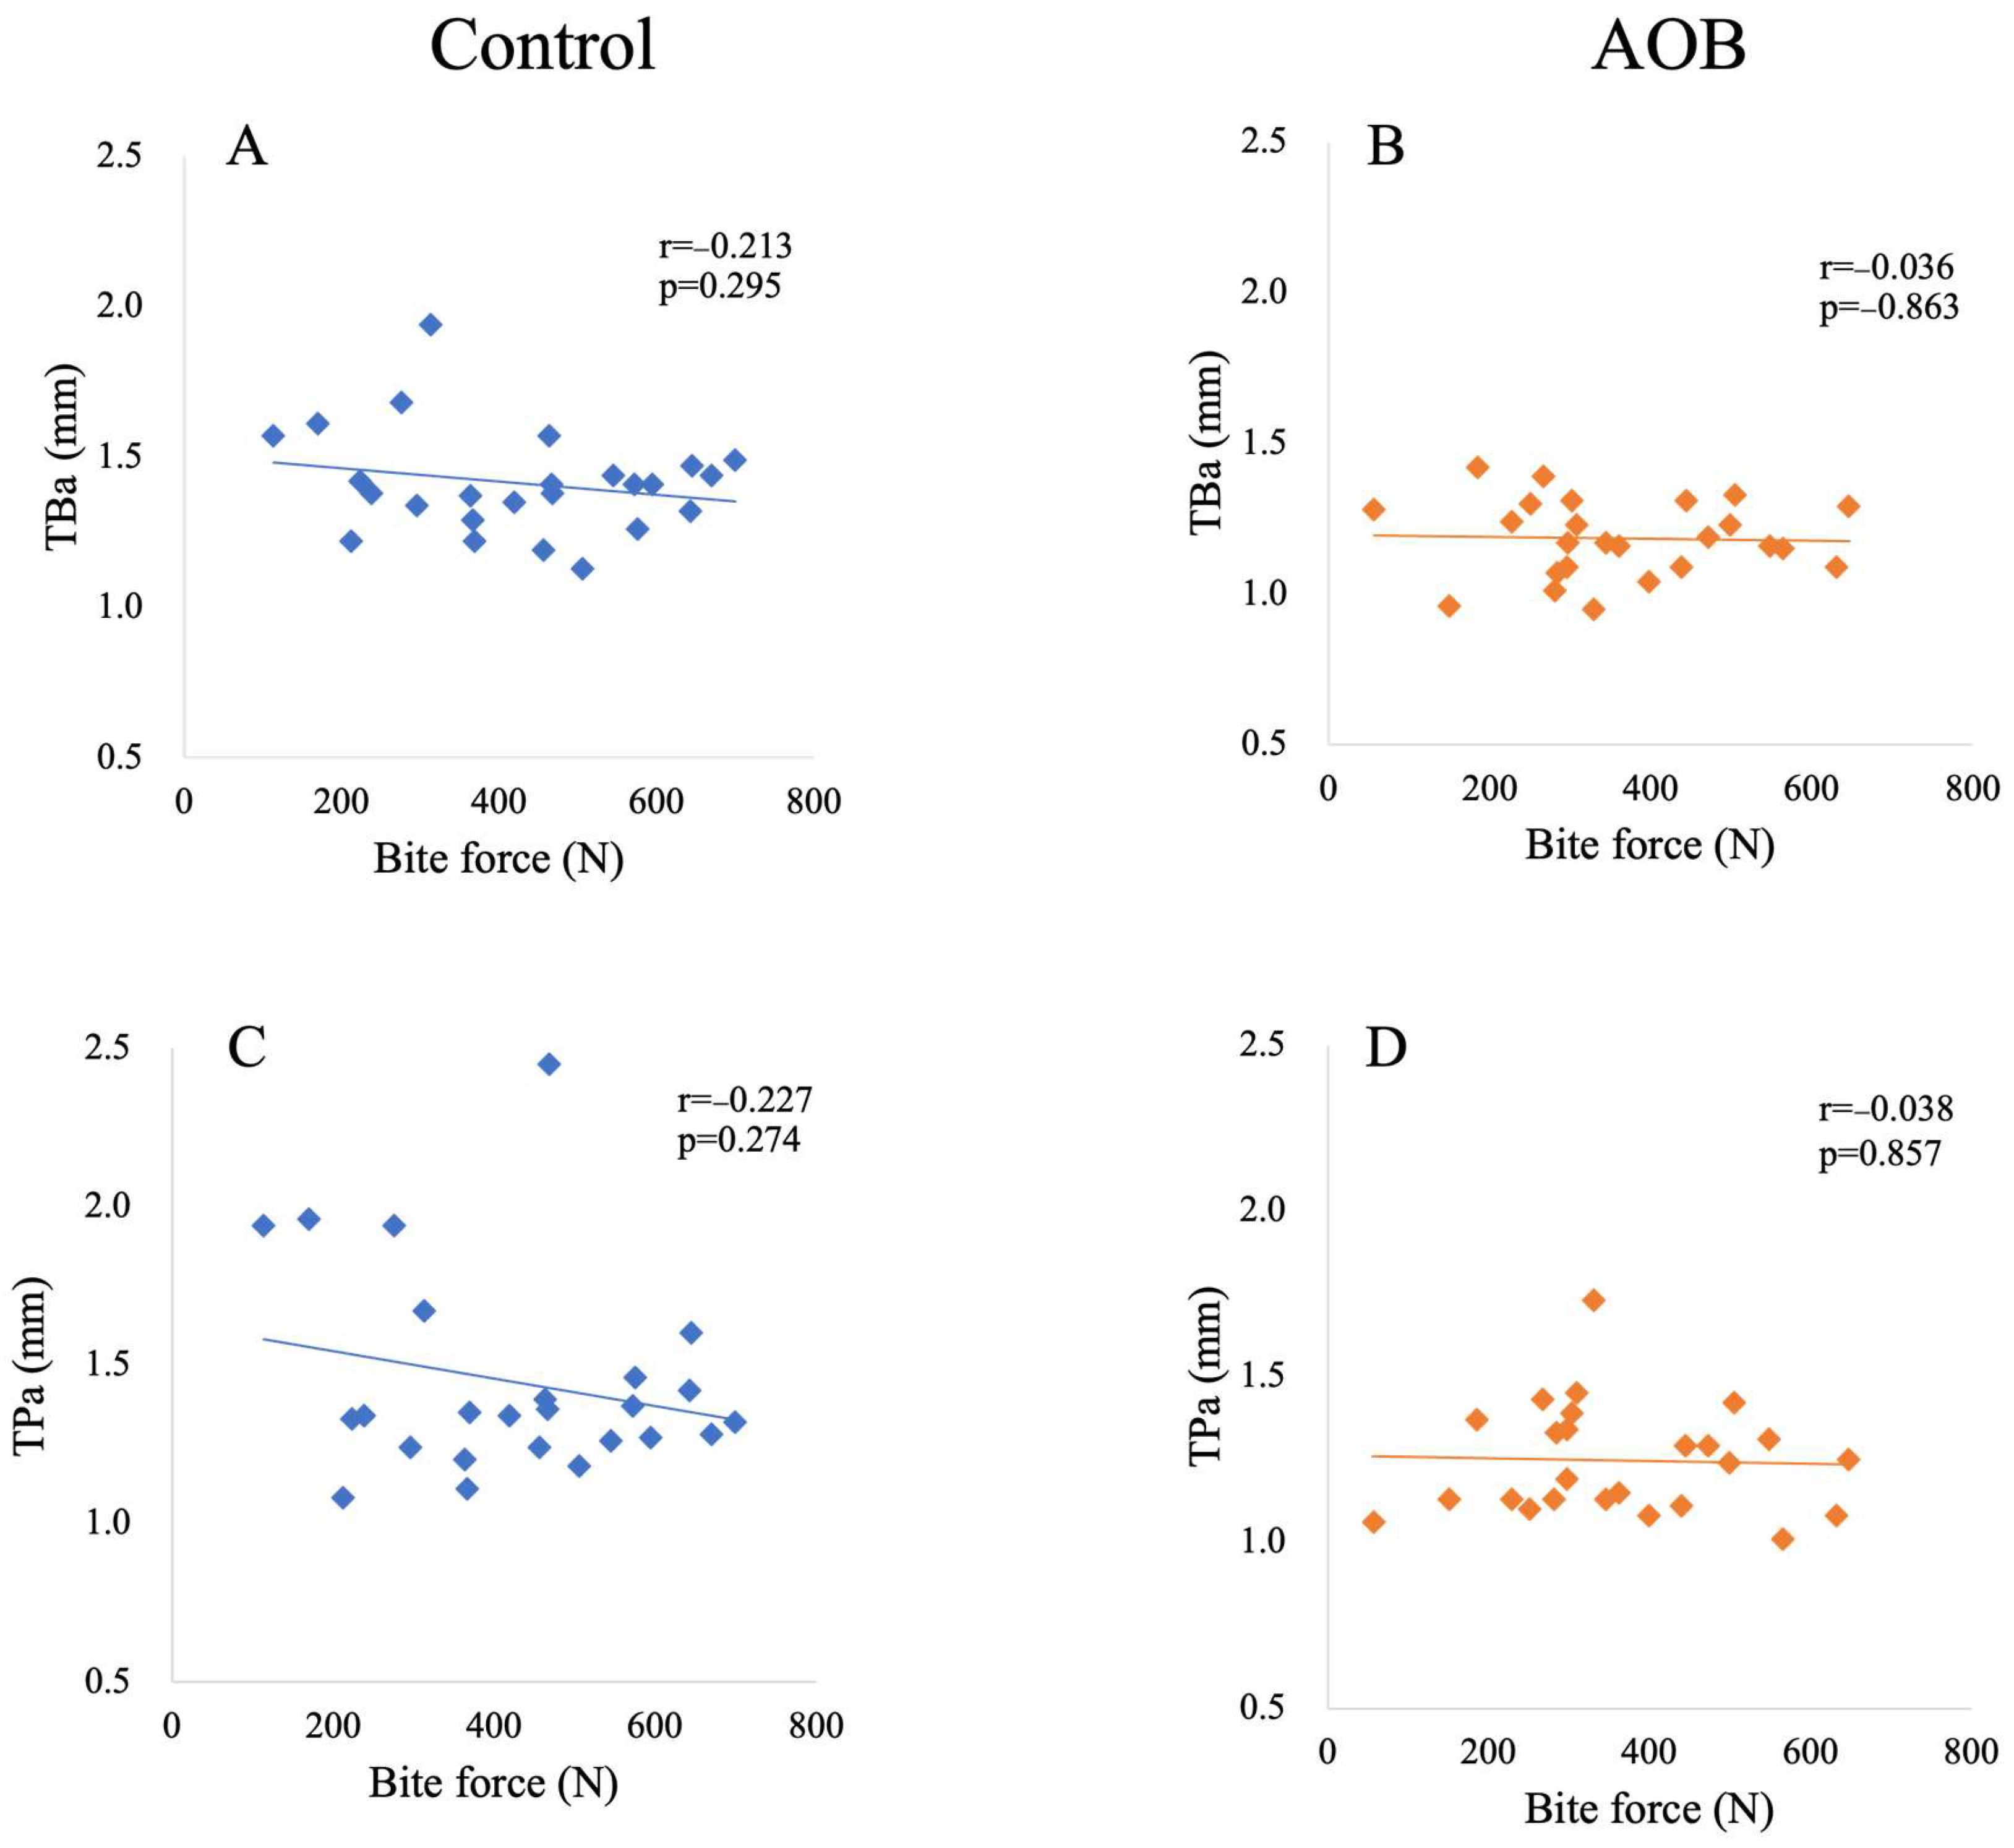

3. Results

| TBa vs. bite force | −0.213 (0.295) | −0.036 (0.863) |

| TPa vs. bite force | −0.227 (0.274) | −0.038 (0.857) |